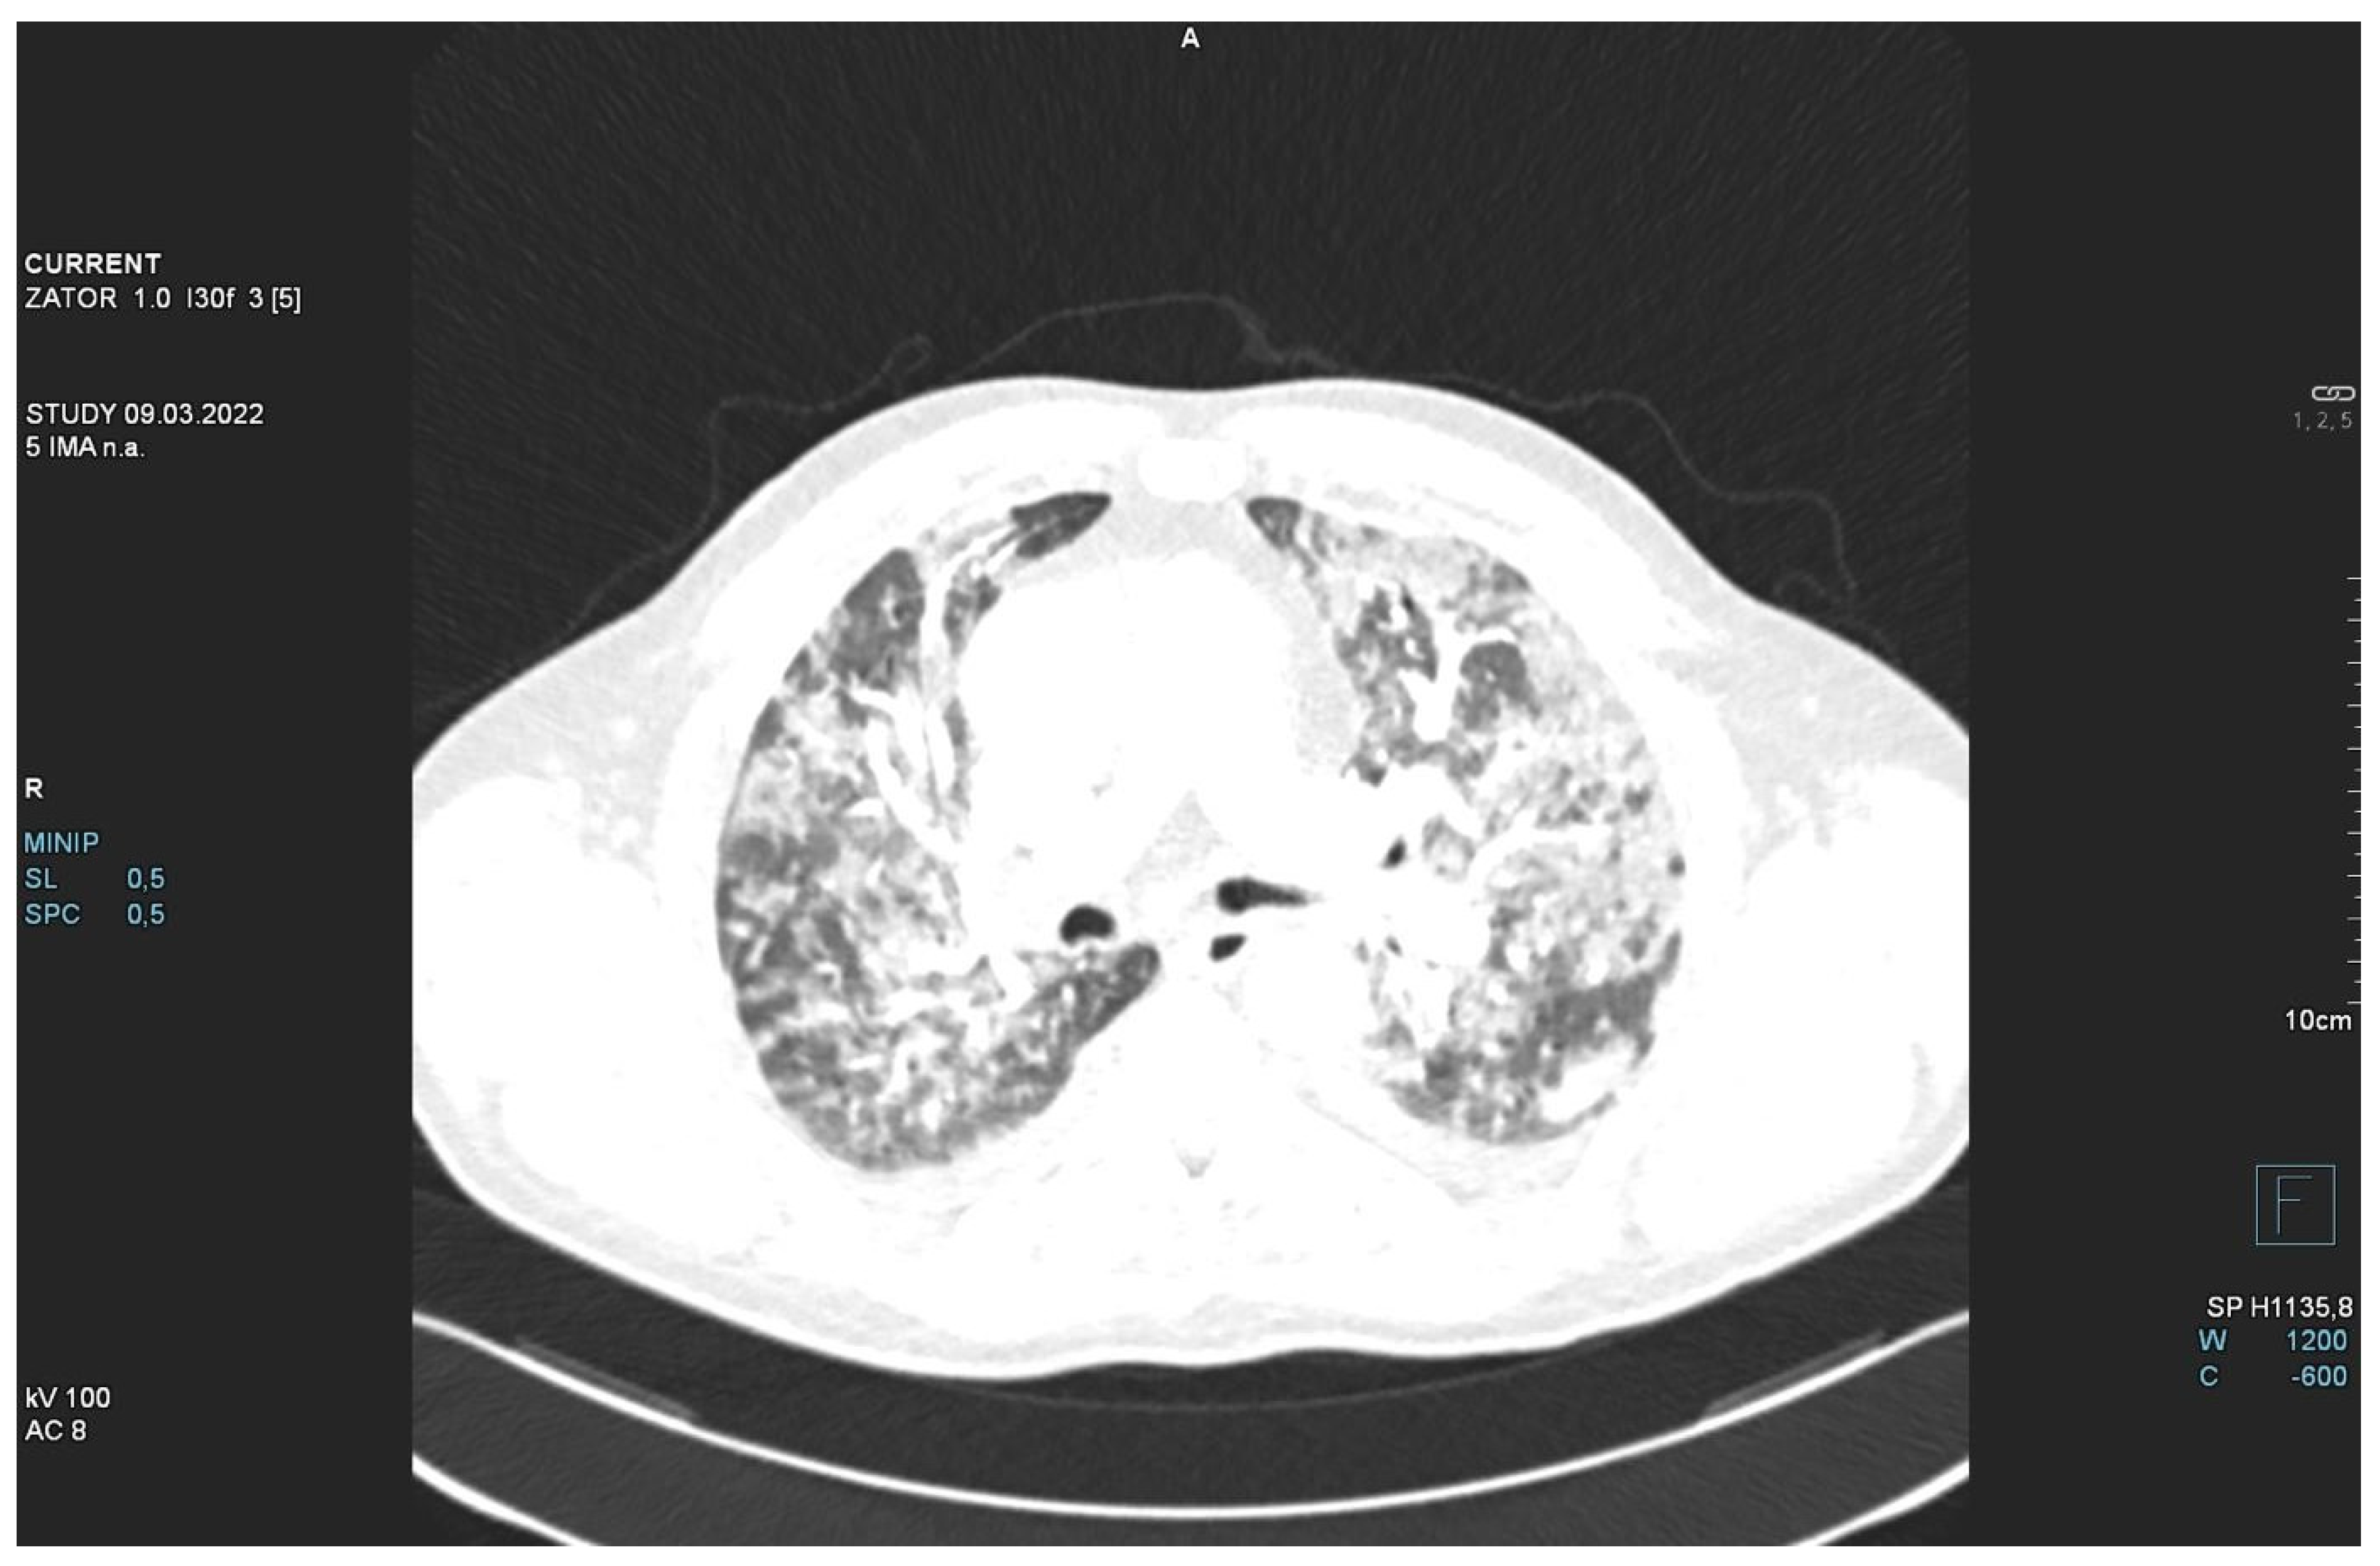

The patient required oxygen therapy, and initially, due to a lack of diagnosis, he received empirically broad-spectrum antibiotics (meropenem, linezolide). On laboratory testing, a further increase in inflammatory and coagulation biomarkers (CRP, ferritin, interleukin-6, D-Dimer, fibrinogen) was observed. Blood cultures as well as a respiratory PCR multitest were negative. Due to the dynamic increase in D-dimers and the elevation of cardiac biomarkers (BNP, NT-proBNP) along with dyspnea, an angio-CT was performed. It excluded pulmonary embolism, but it revealed widening of the pulmonary trunk and pulmonary arteries, as well as alveolar compaction in both lungs and bilateral pleural effusion. Pulmonary edema was diagnosed (Figure 2, Figure 3 and Figure 4).

Figure 4.

Angio-CT scan.